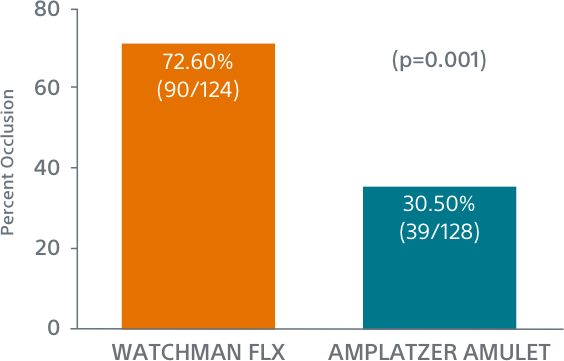

WATCHMAN FLX Demonstrated Statistically Superior Complete Occlusion** vs Amulet (p=0.001)

**Complete LAA occlusion defined as no visible peri-device leak (PDL) and absence of contrast patency in the distal LAA (LAA/left atrium Hounsfield ratio <0.25)